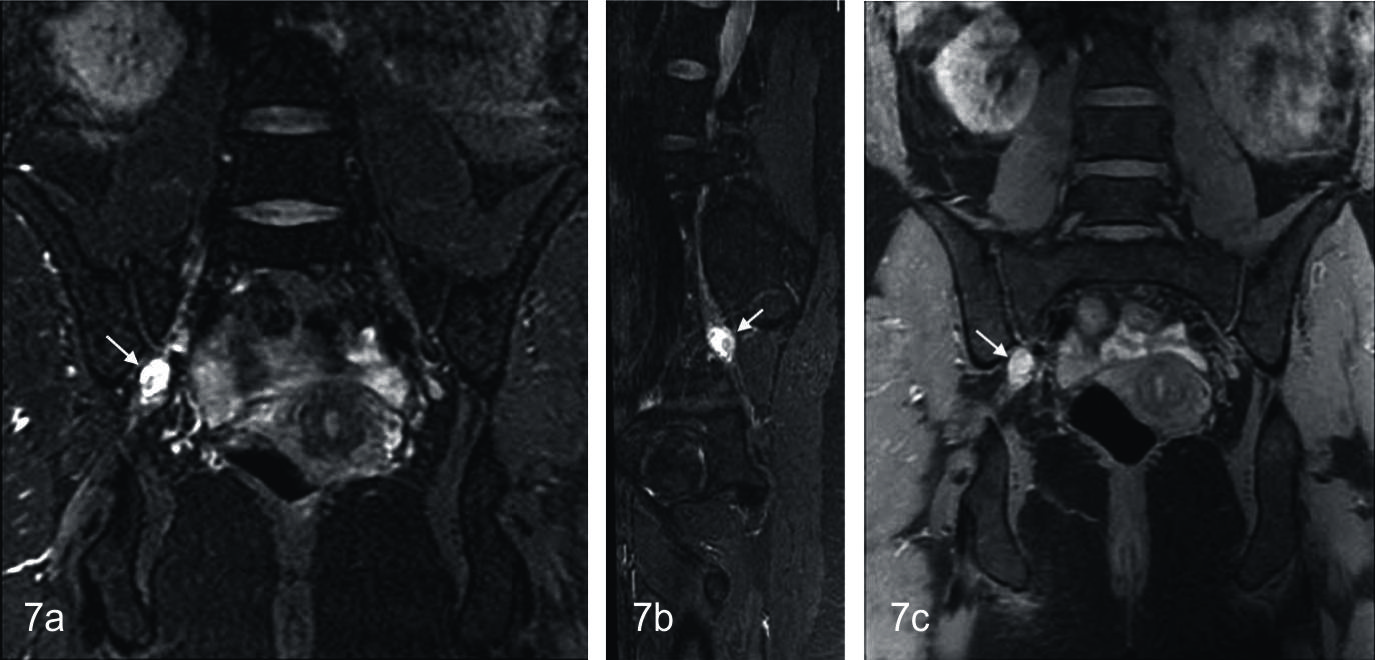

Figura 7

Neurofibroma en paciente de sexo femenino de 33 años.

Secuencia neurográfica IDEAL en ponderación T2, (a) plano coronal, (b) reconstrucción oblicua; donde se observa engrosamiento nodular de morfología fusiforme, a nivel del tronco lumbosacro derecho (flecha); (c) Secuencia IDEAL en ponderación T1 con saturación grasa, con contraste endovenoso. Se observa intenso realce homogéneo de la lesión.